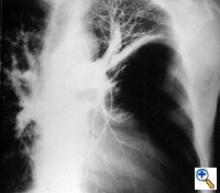

| Figure 3: Chest x-ray of a large bulla with true infection; after the appropriate medical treatment fever, hemptysis and fluid level persisted and the bulla was resected. |

Surgery is generally indicated to modify the functional status of the underlying lung by (1) relieving restrictive changes; (2) increasing compliance and airway caliber; (3) improving V/Q ratio; and (4) decreasing the physiologic dead space. These goals are easy to obtain in patients with enlarging bullae and minimal underlying lung disease. These are the best candidates for surgery and optimal results can be expected. Surgery is also indicated to treat complications related to the bullae, such as pneumothorax, true infection (Figure 3), hemoptysis, cancer (Figures 4, 5), and pain.

The preoperative work-up should always include clinical and functional evaluation (arterial blood gas analysis and pulmonary function tests with plethysmography), chest x-ray (Figure 6), computed tomography (Figure 7), and V/Q scan (Figure 8). Pulmonary angiography (Figure 9) has been reported to show some advantages in evaluating the underlying lung; however, it is not routinely performed.